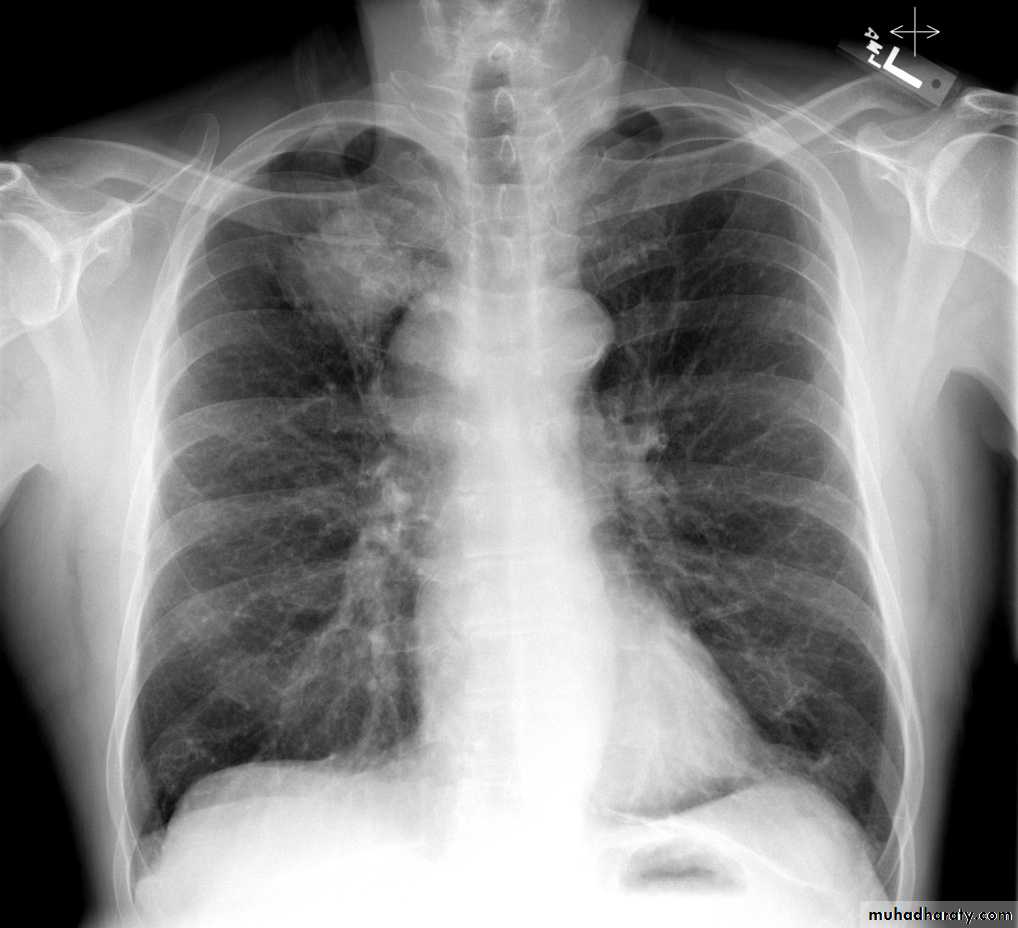

Lobular consolidation ( broncho or lobular pneumoniaCXR of adult ,PA and lateral views show:Patchy consolidation in both lung fields (diffuse) mainly in the lower zonesNormal heart size

Very important to consider that pulmonary edema in normal sized heart have close similar appearance to broncho pneumonia

The important Golden Key differentiation is the cardiac size being enlarged in pulmonary edema .

Interstitial pulmonary edemaCXR of adult , PA view shows:Bilatral patchy opacity involving mainly lower lung fields with enlargement of cardiac shadow

Pulmonary edema ( alveolar pulmonary edema)CXR of ault ,PA view shows:Bilateral patchy opacity mainly in the middle zones of the lungs (Bat wing sign )Cardiomegaly

Bat wing sign ( alveolar pulmonary edema)CXR of adult male, PA view shows:Bat wing sign, Cardiomegaly